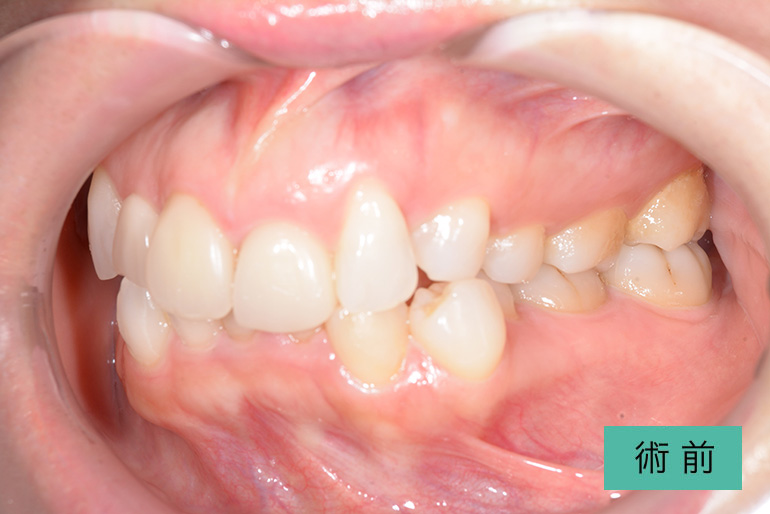

インビザライン③

| 治療内容 | 歯並びをキレイにしたい。 口腔内容積を狭くしないように、歯列を拡大し非抜歯で矯正をする。 |

|---|---|

| 治療期間・回数 | 約6年、80回 |

| 費用(税込) | ¥880,000(マウスピース矯正) ¥620,000(セラミッククラウン) ※自由診療 |

| リスク・副作用 | 歯肉退縮、知覚過敏、後戻り |